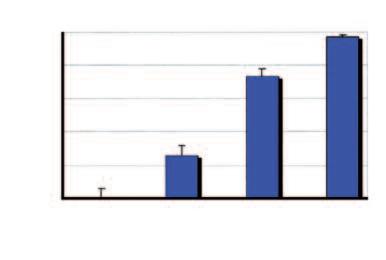

Aumento del numero dei decessi dovuti al cancro nei diversi gruppi di età, dal 1970 al 2000

Età dei pazienti 70 - 79 anni

Età dei pazienti 60 - 69 anni

Età dei pazienti 50 - 59 anni

Dati statistici per gli USA, dati comparabili per l’Europa. Fonte: Journal of the American Medical Association, 2005